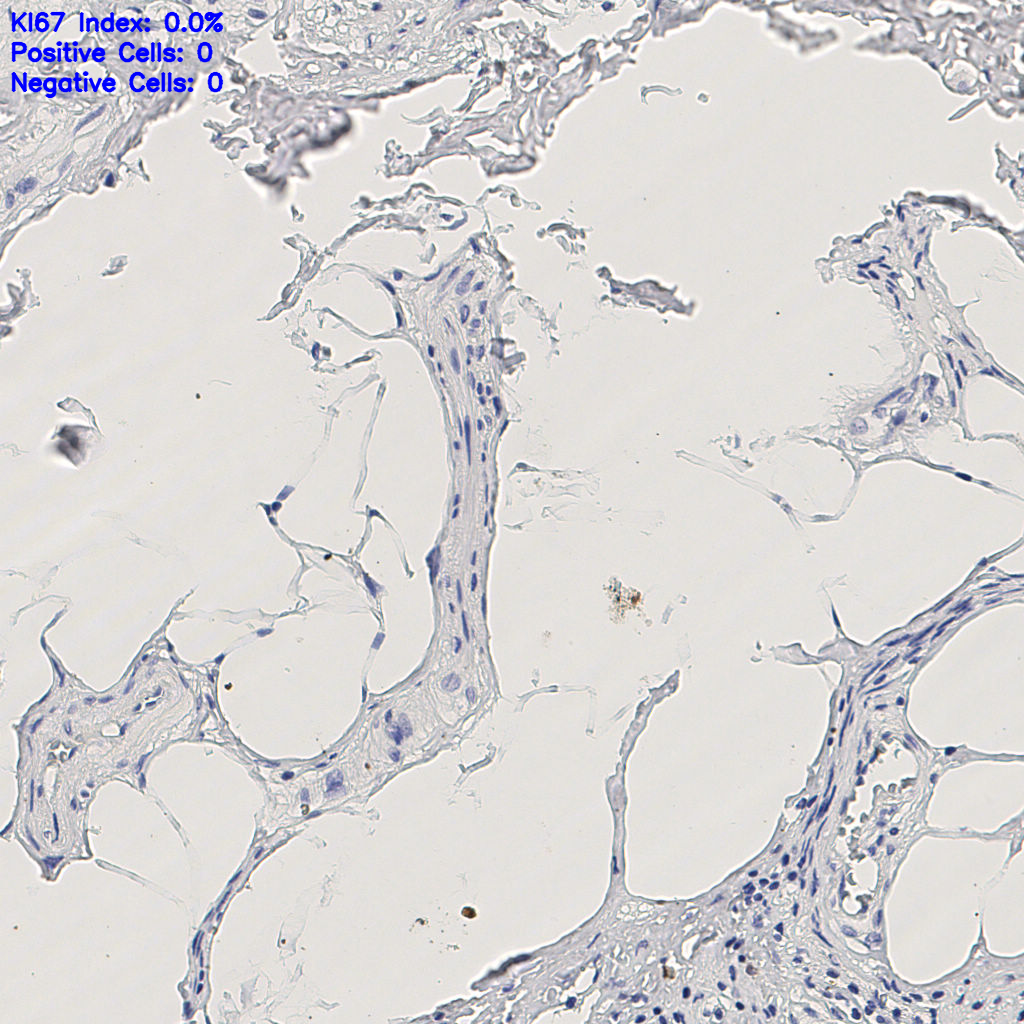

缩略图

slice_7_21_x6272_...

标记后

标记前